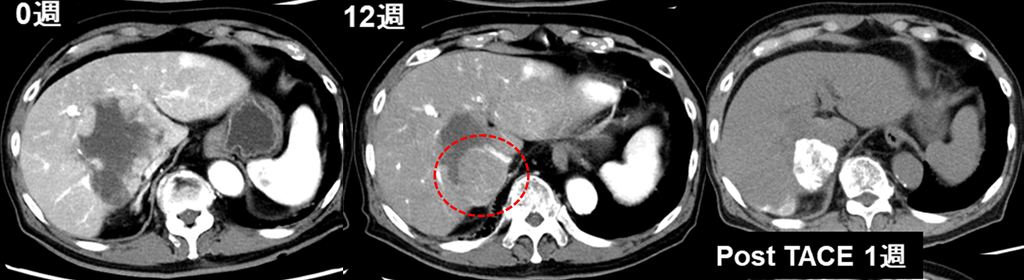

There are various methods of treatment for hepatocellular carcinoma, including hepatectomy, radiofrequency/microwave ablation, catheter therapy (hepatic arterial chemoembolization, hepatic arterial infusion), radiation therapy, systemic drug therapy, and liver transplantation. The Department holds weekly joint conferences with the Department of Gastroenterological Surgery, the Department of Diagnostic Radiology, and the Department of Radiotherapy to provide the most appropriate treatment for each patient's condition. Furthermore, for advanced liver cancer, we aim to achieve a liver cancer-free state by appropriately combining systemic drug therapy with surgery, local therapy, and catheterization, in addition to a single treatment (Figure). Radiofrequency/microwave ablation therapy is also performed for metastatic liver cancer, depending on the disease status.

Figure 3. After 12 weeks of drug therapy, the majority of the tumor showed a shrinking trend. Catheterization was added for residual disease.